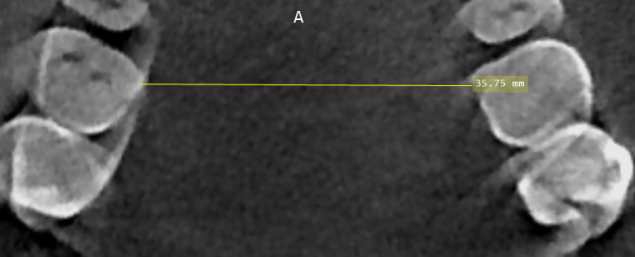

Guys , how do orthodontists actually check up if u have a narrow palate or not . Cuz Iam quite sure I have one . My paltal width is about 27 mm on a paper . Got actally diagnosed with it by an orthodontist how some how " hid it " without using an actuall paltal expander .

Like how do they even check ?